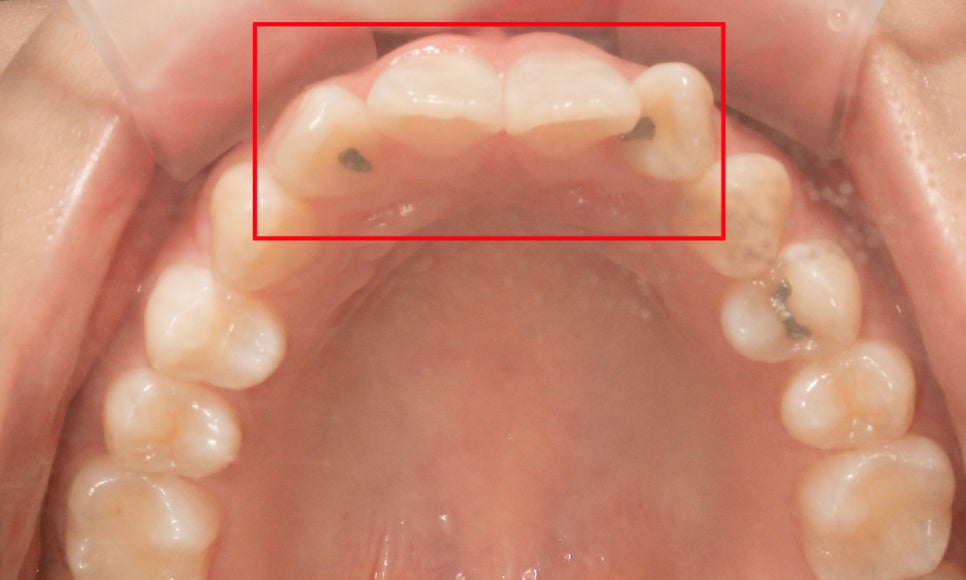

상악 전치부의 치아 배열을 확인하면

위처럼 중절치가 설측으로 미세하게 뻐드러져 있고

측절치의 각도는 대략 90도 정도로 틀어진 모습인데요,

위와 같은 case의 경우 1급 부정교합에

해당하거나 혹은 부정교합 증상 없이

몇 개의 치아만 회전되어 있다면 (앞니틀어짐)

문제가 있는 치아들을 부분적으로

교정할 수 있습니다.